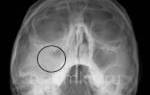

После проведения операции пациент направляется на рентген, чтобы специалист мог оценить результат прокола. Для улучшения состояния носовых проходов пациенту рекомендуется проводить санацию фурацилином в домашних условиях, что необходимо делать регулярно в течение полугода после хирургического вмешательства.

Только отоларинголог способен установить точный диагноз. Для этого требуется провести анализ крови, а также выполнить рентгеновское и компьютерное томографическое исследование носовых пазух.

Особенно опасная ситуация возникает, когда кровь и гной накапливаются в организме, и при этом жидкости не выводятся естественным образом. Определить данную проблему можно с помощью ультразвукового исследования и рентгенографии. Пациент испытывает острые болевые ощущения в носовых пазухах, температура тела повышается, а также наблюдается неприятный запах из носа.